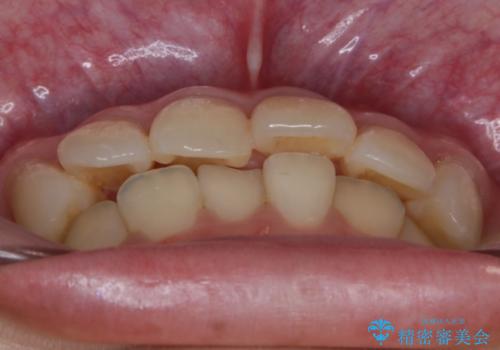

- 笑った時の歯の見え方を治したいとのことで矯正相談にいらっしゃいました。

一見そこまで大きなガタつきはないようにも見えますが、前歯の角度の不揃いや噛み合わせのズレなどから見え方に影響が出てしまっていました。

抜歯は全く必要のないレベルのガタつきだったため、マイクロインプラントを用いて歯全体を後方に移動させていくことできれいな歯並びを獲得することができました。